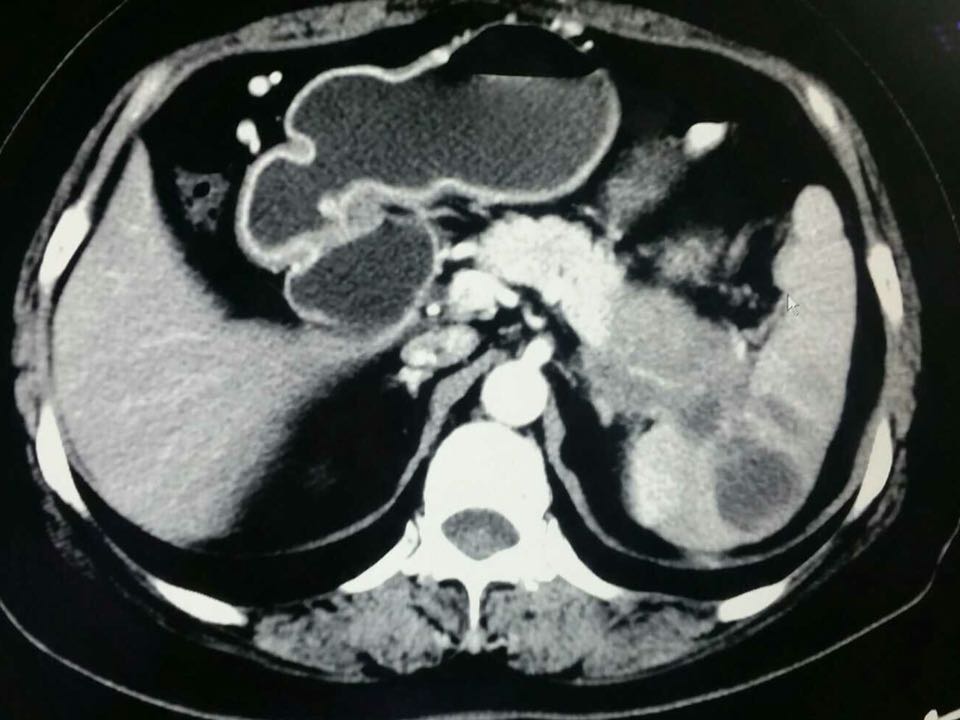

女,66岁,患者左腹隐痛半年余,做ct如下,各位怎么考虑?

胰腺癌